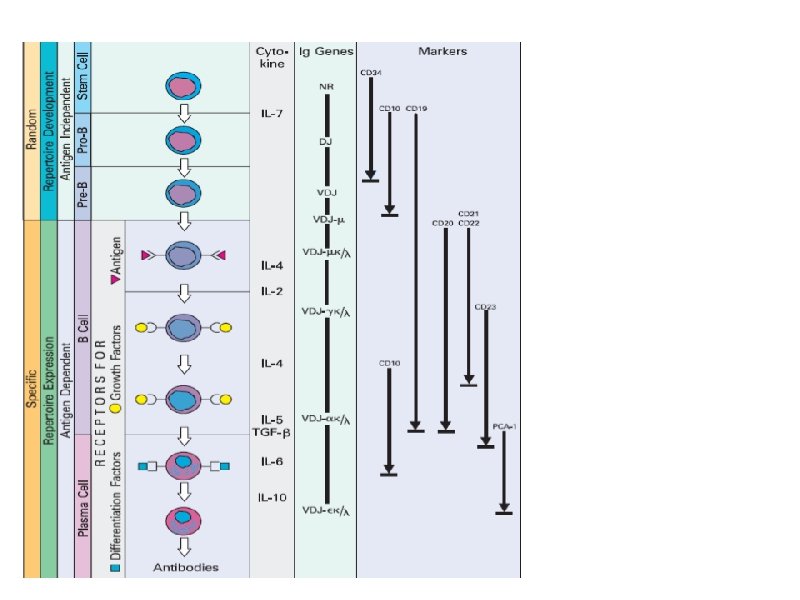

Этапы созревания лимфоцитов